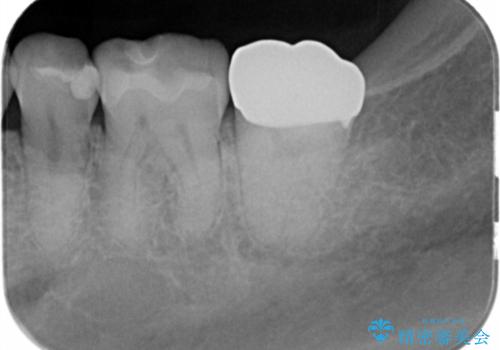

- 銀の詰め物が取れたとのことで来院。

詰め物の下には虫歯がありました。

白い物で治療して欲しいとのことで、セラミックの詰め物だと詰め物の範囲が大きく、割れてしまう可能性があるので

ジルコニアクラウン(被せもの)で治療を行いました。

銀の詰め物はかなり昔に治療されたそうです。

銀の詰め物は虫歯の再発リスクが高く、歯に痛みが出てしまうと歯の神経の治療もしないとならなくなってしまいます。